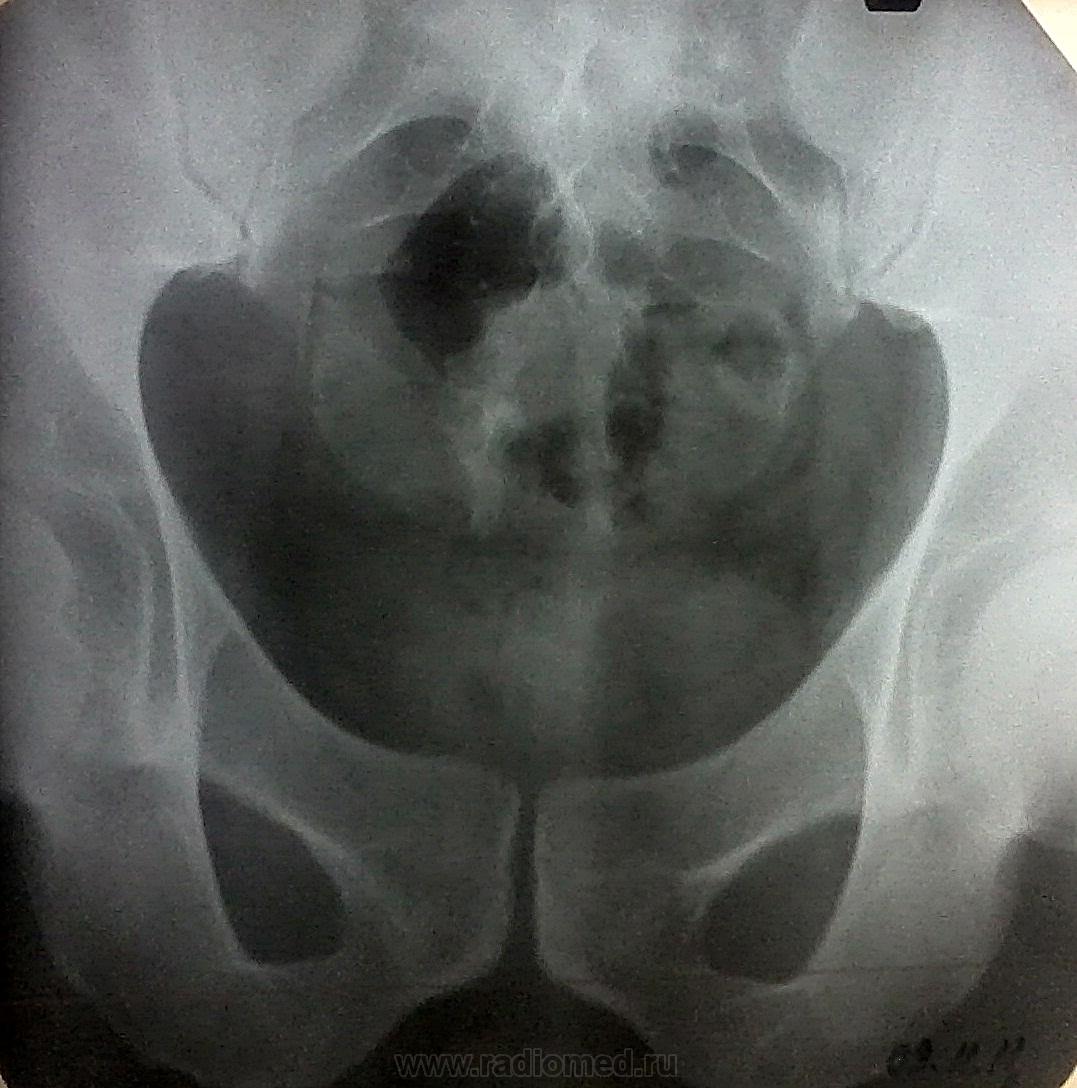

Мужчина, 43 года, жалуется на боли в области крестца и копчика усиливающиеся в сидячем положении около года. около 2-3х дней назад боли значительно усилились, сидеть не может. при осмотре проктологом и урологом патологии не выявлено. госпитализирован в хирургическое отделение с диагнозом: Кокцигодиния с выраженным болевым синдромом. Ваше мнение?

Я думаю, что без повторного прямого снимка с удовлетворительной подготовкой кишечника (а в условиях стационара сам бог велел!) и без нормального бокового дело с места не сдвинется - а то какая-то дополнительная костная тень в правой фораминальной области крестца мерещится...